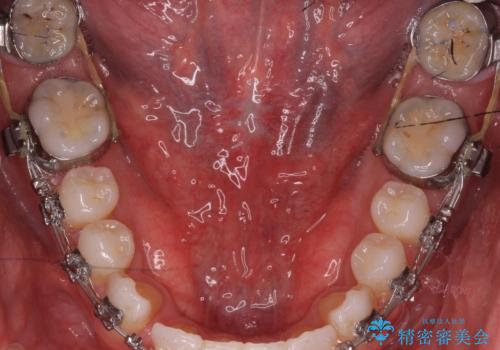

舌小帯の切除

- 他院で矯正治療をしているが、滑舌も気になるため舌小帯の切除を希望し来院されました。

手術自体は当日での処置が可能です。

抜糸は1週間から2週間の期間を置いた後治癒を確認してから行います。